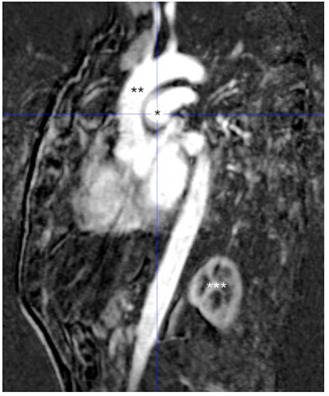

Observe a imagem a seguir.

Sobre a imagem acima, é correto afirmar que